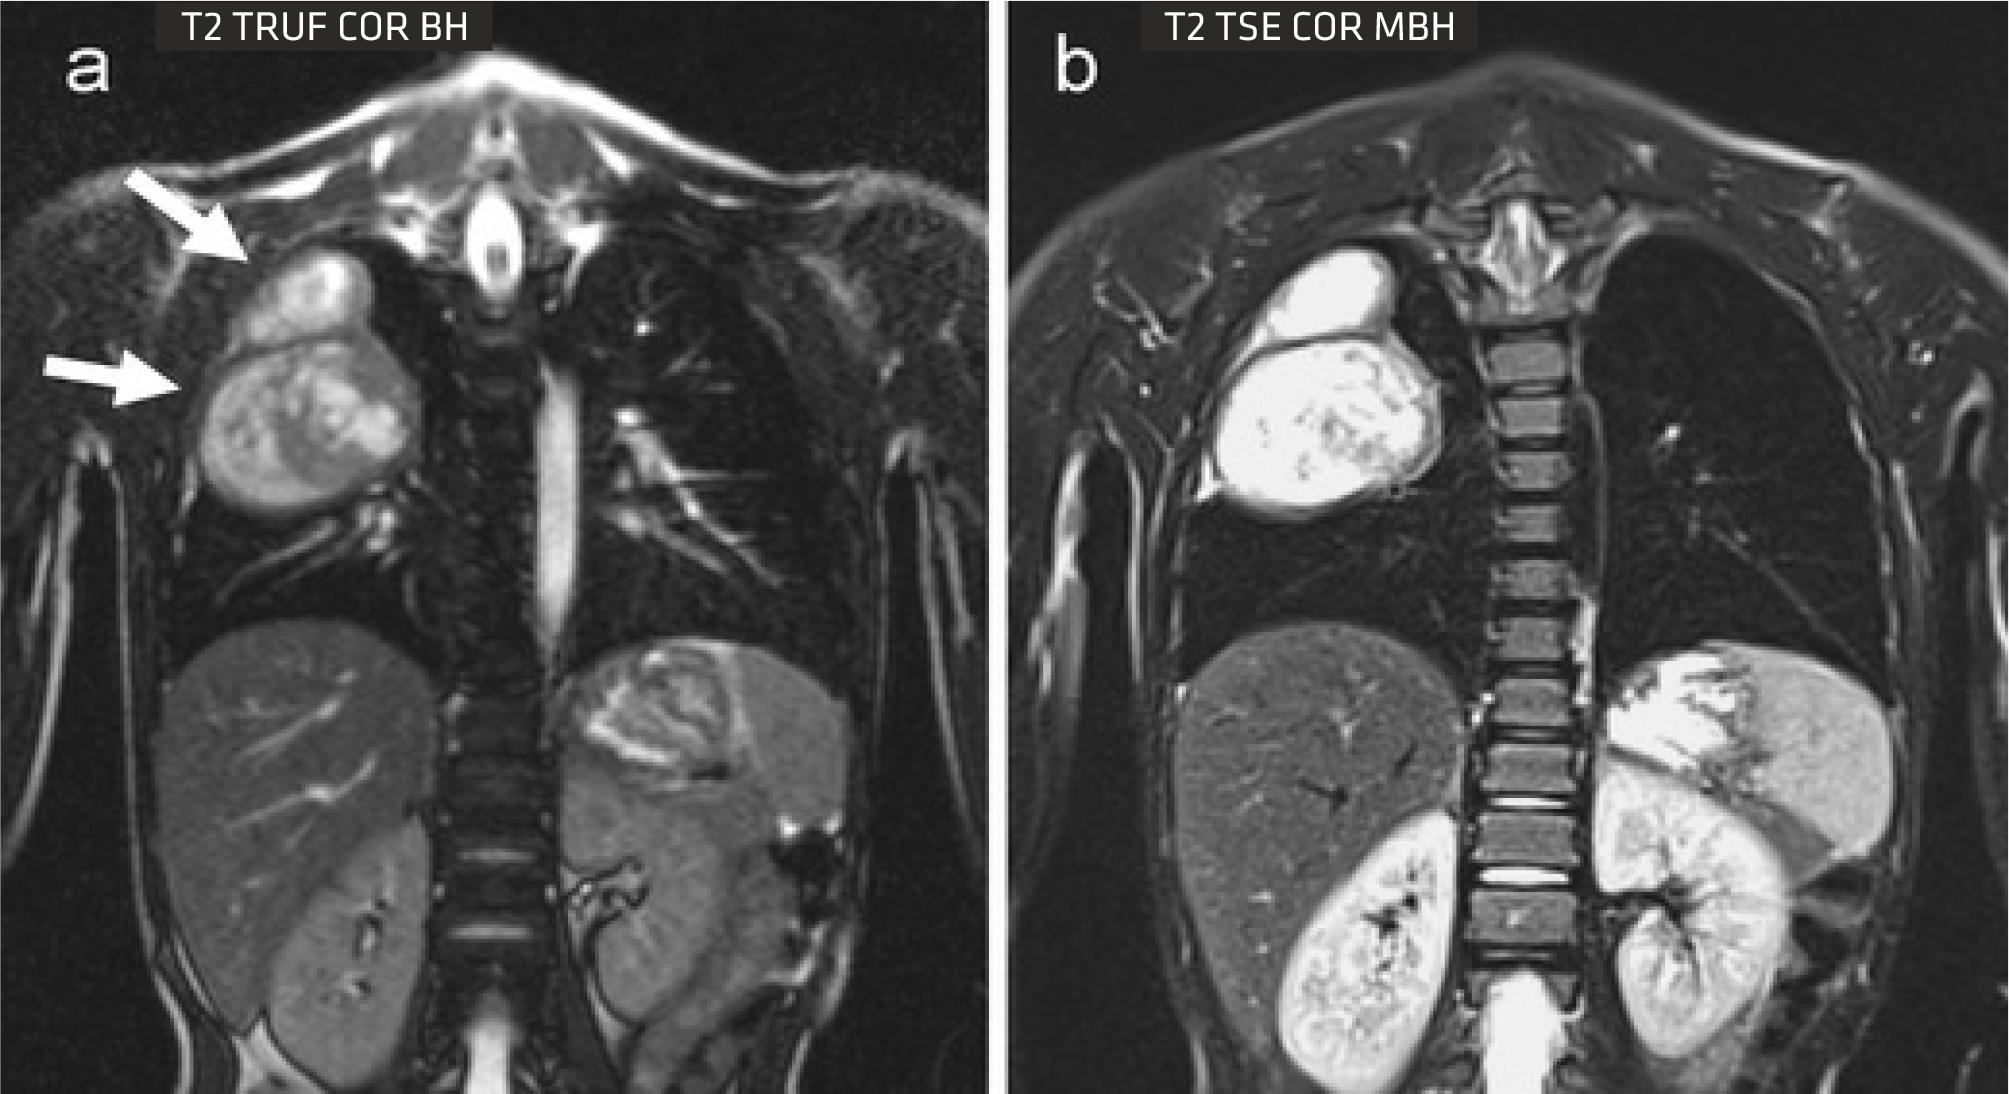

The Sequoia Healthcare Clarity 1.5T oers comprehensive body imaging solutions with advanced tools tailored for patients. Its Free Breathing (ARCUS) MR Imaging protocols primarily utilize either breath-holding techniques or respiratory gating to eectively minimize motion-related artifacts, ensuring clearer and more accurate imaging results.

mLIVE

A visualization platform is available, granting access to sophisticated postprocessing technology. Leveraging the Proton Density Fat Fraction (PDFF) method, it automatically segments and measures fat within the liver by creating quantitative fatfraction maps.